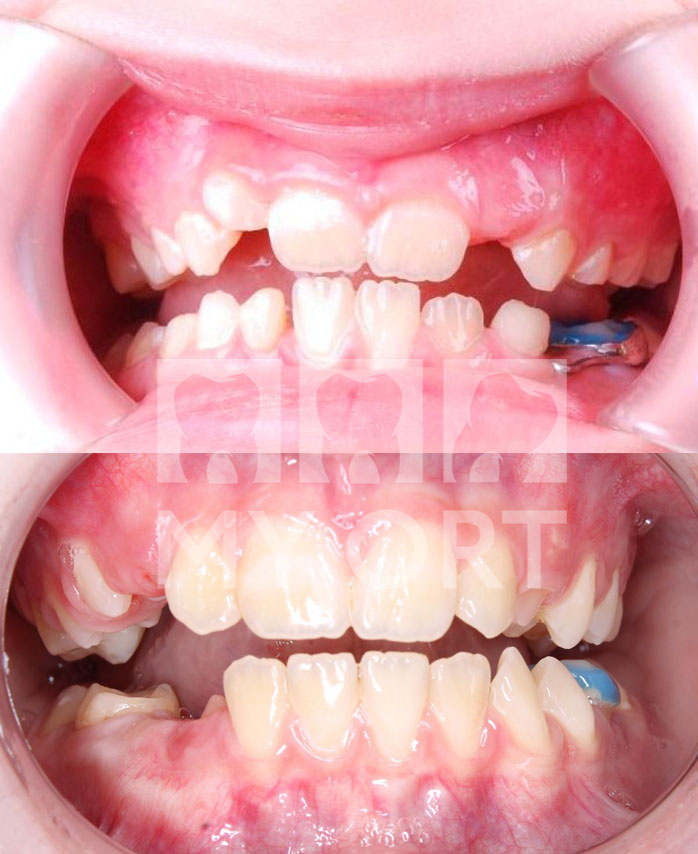

Результаты лечения

Мама пациентки отметила видимые изменения уже в первые месяцы ношения второй каппы, а за лето мы увидели отличный результат - изменилось лицо, профиль.

Чего мы смогли добиться во время лечения

1. Улучшение лицевого профиля.

2. Устранён дефицит места для зубов.

3. Скорректирован наклон окклюзионной плоскости.

4. Уменьшена ретрузия (нормализация высоты прикуса).

5. Исправлен дистальный прикус.

6. Частично устранена скученность зубов.

Улыбка До и После

Посмотрите, что у нас получилось:

До и после